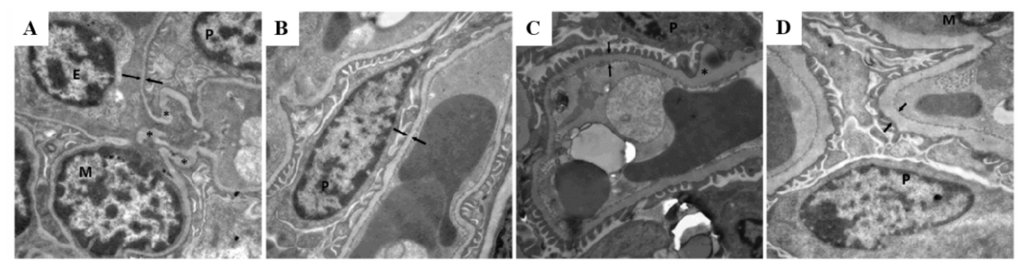

Figure 3.

Electron photomicrographs showing age-related growth of glomerular basement membrane (GBM) thickness in gckw/− mice. Electron photomicrographs from gckw/w mice (A, B, C and D for 26, 40, 60 and 85 weeks of age, respectively) and gckw/− mice (E, F, G and H for 26, 40, 60 and 85 weeks of age, respectively) (six mice (n = 6) were examined in each group, with three glomeruli examined per mouse; representative images shown). Magnification is ×12,000. Opposing paired double arrows indicate the GBM. M, E, and P designate mesangial cells, endothelial cells, and podocytes, respectively. * Indicate prominent irregularities in the basement membrane. I: Quantification of the GBM thickness. * p < 0.05, ** p < 0.01 vs. age-matched gckw/w mice.

To determine whether gckw/− develop kidney complications, the morphology of kidney tissue was examined. At 26 weeks of age, gckw/− mice show a kidney morphology that is normal in appearance and is similar to that of age-matched wild-type mice (compare Figure 2A,E). As gckw/− age, a gradual increase in the amount of mesangial matrix is observed (see Figure 2F–H for gckw/− mice at 40, 60, and 85 weeks, respectively) compared with their age-matched controls (Figure 2B–D at 40, 60, and 85 weeks, respectively). These results show that renal lesions start at about 40 weeks of age in gckw/− mice, and that these lesions gradually become more aggravated with age. The thickness of the glomerular basement membrane (GBM) shows a similar pattern to the mesangial matrix (Figure 3I). No change in GBM thickness was observed in 26-week-old gckw/w compared with gckw/− mice (Figure 3A,E), however, at 40 weeks of age gckw/− mice showed significantly thicker GBM compared with their age-matched wild-type mice (compare Figures 3B,F, statistical analysis in Figure 3I). The GBM thickness in gckw/− mice continued to grow larger at older ages (Figure 3).

Measurements of serum triglyceride and total cholesterol concentrations (Table 1), which showed no difference between knockout and wild-type mice, indicated that the liver-specific GCK deletion leads to a state of mild diabetes and may have no effect on lipid metabolism. Serum urea nitrogen and creatinine levels are two commonly used measures of kidney function. The concentrations of urea nitrogen and creatinine showed no difference between the knockout and wild-type mice except the creatinine levels in 40-week-old gckw/− mice where they showed a transiently higher level of serum creatinine compared with age-matched wild-type mice (Table 1). While the increase of serum creatinine in 40 weeks gckw/− mice was transient, it attracted our attention, as mild hyperglycemia may cause kidney complications. Creatinine is a waste product generated by the degradation of creatine in muscle, therefore its levels should depend upon muscle mass [25]. Muscular young or middle-aged adults may have more creatinine in their blood than the norm for the general population, while older individuals may have less creatinine in their blood [25]. Since serum creatinine is an important indicator of kidney function, elevated creatinine levels may signify impaired kidney function or kidney disease, however, no uniform standard exists for mouse serum creatinine levels. The normal clinical range for creatinine in humans is 44–106 μM, with levels > 530 μM being a sign of kidney disease and in some pathological conditions it can exceed 1000 μM [26]. In the 40-week-old gckw/− mice, the increase in serum creatinine levels was less than one-fold, compared with age-matched wild-type mice, suggesting that only slight kidney damage existed in these mice. The serum creatinine level of gckw/− mice was reduced after 60 weeks, which might have been due to the loss of muscle with age. Kidneys have a very strong compensatory ability, and creatinine levels can continue to increase until more than half of the kidney function has been lost. Although kidney damage progressed with age, the renal complications occurring in the gckw/− mice was small, thus the function of kidneys may still have been within the normal range. While changes in creatinine levels may have been minimal, increased concentrations of protein in the urine of gckw/− mice of 40 weeks of age and older, compared with age-matched gckw/w mice (Table 1), indicated that they had kidney damage. Furthermore, PASM staining and electron micrographs of the kidneys of gckw/− mice 40 weeks of age or older illustrated histological evidence for kidney complications that increased with age (Figures 2 and 3). Further studies, measuring water consumption, eGFR, and urine albumin levels, should provide more information on the extent of damage to the kidneys in the gckw/− mice.